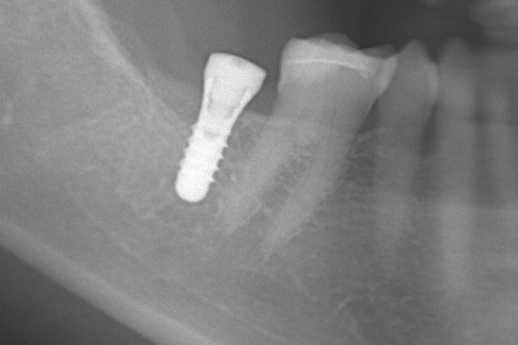

インプラント

重度虫歯からのインプラント・入れ歯治療(*^-^*)